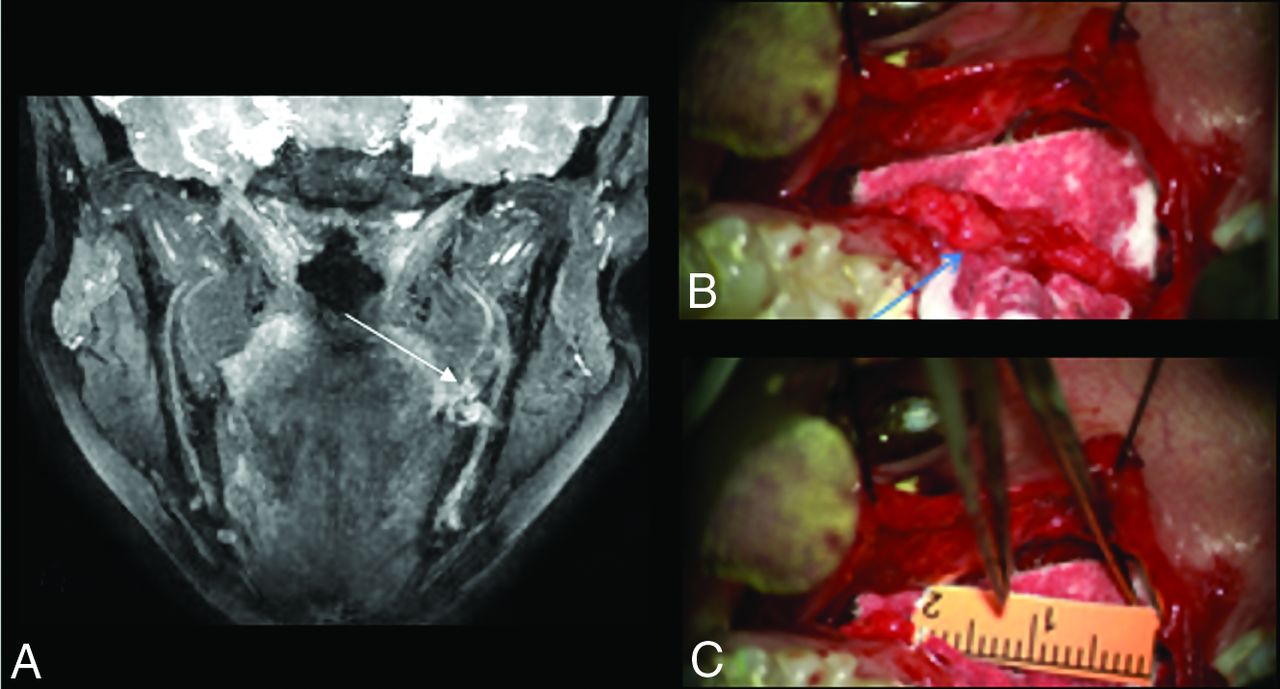

NST was performed by the same experienced oral and maxillofacial surgeon. Thirteen of 24 patients from this group underwent surgery of 13 nerves, and injuries were graded intraoperatively by using the Sunderland classification criteria in Table 2 (Fig 4). Unclassified nerve injuries or indeterminate findings on NST and intraoperatively were recorded (On-line Table 2).

A, MIP 3D PSIF coronal image shows class IV/V injury of the left LN with excessive granulation and possible discontinuity of its distal end (long arrow). B, On surgery, it was also called class IV/V injury (arrow) with excessive scarring and granulation tissue and was resected. The final gap was 16 mm (C) and an allograft was placed for nerve reconstruction.